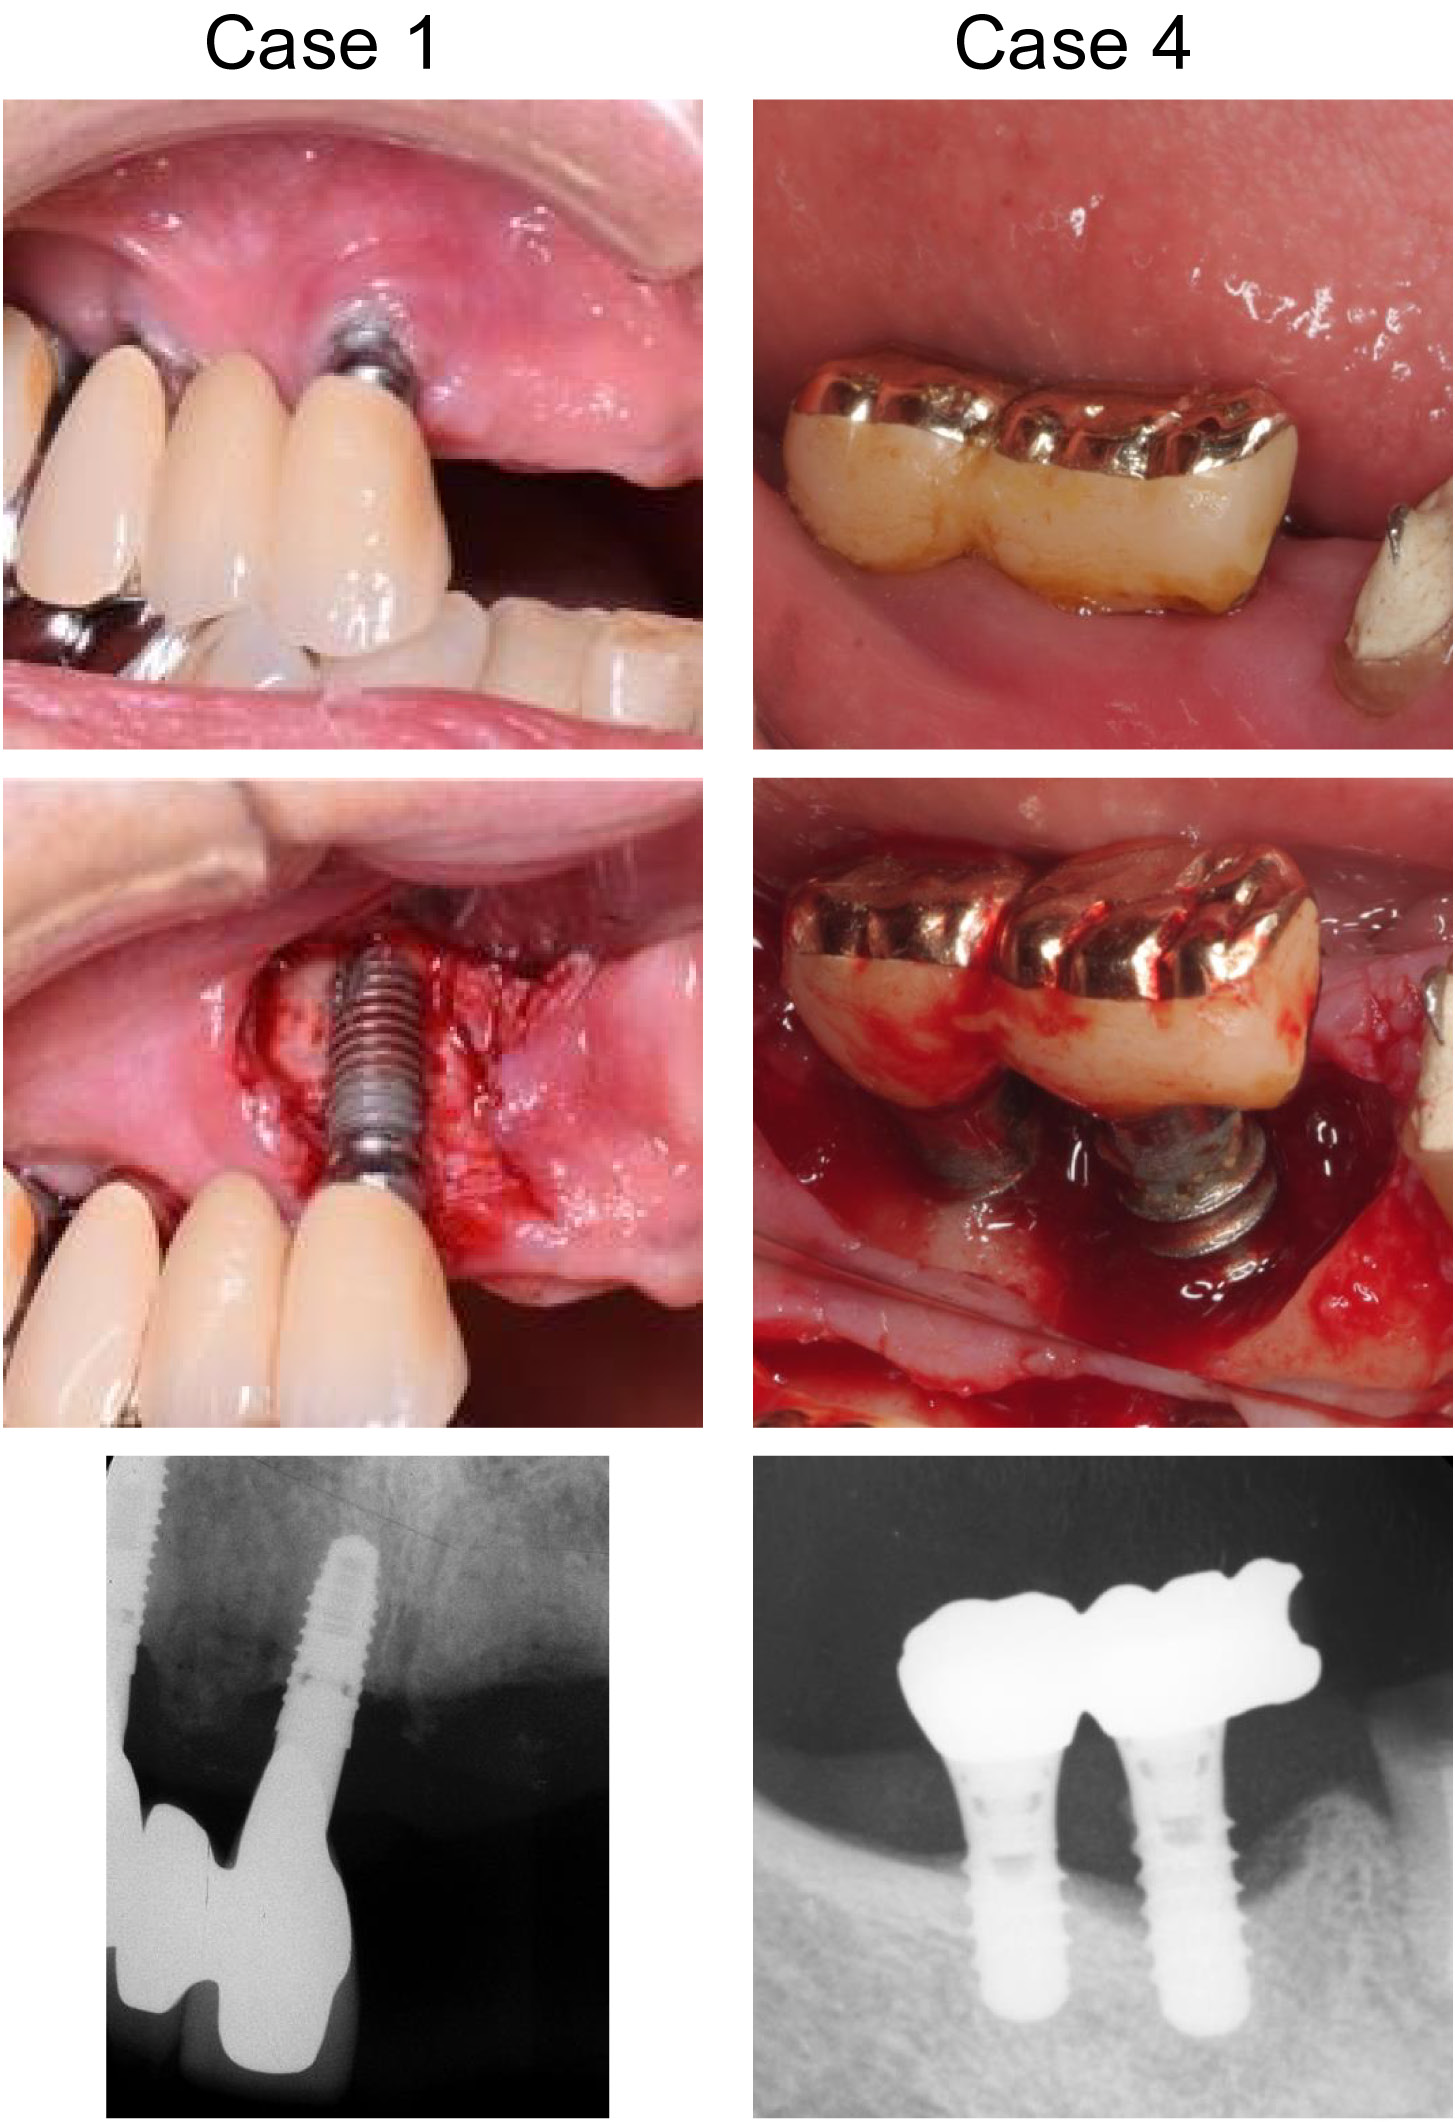

The demographic information of the participants and the characteristics/locations of the treated implants are presented in Table 1. The levels of peri-implantitis for those implants ranged from moderate to severe (4.2–8.7 mm of bone defect depth) in terms of bone resorption, with 6–10 mm of probing pocket depth (PPD), and BOP observed at all sites. Figure 2 presents the clinical photographs and radiographs of 2 cases (case 1 and case 4).